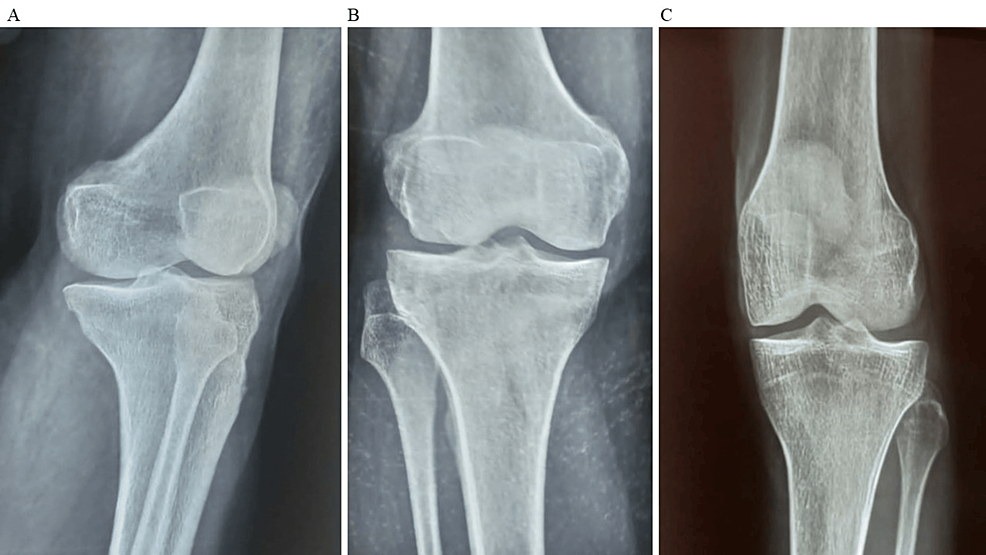

除了骨關節炎外,15名參與者還被發現患有骨缺損,占該隊列的30%。這些缺損包括各種情況,例如骨折、退行性骨病或先天性畸形,突顯了研究中涉及的骨科問題多種多樣。下圖1顯示了開始干細胞治療之前的骨骼側視圖和前后視圖。

診斷的詳細分布為了解研究參與者所遇到的骨科疾病范圍提供了關鍵見解。了解這些診斷的普遍性和多樣性對于制定治療策略和評估干細胞療法在不同骨科環境中的療效至關重要。使用各種方法評估治療結果。對于評估疼痛強度的VAS,參與者的疼痛從基線到六個月顯著減少(圖1)。平均VAS評分從基線時的7.4±1.1下降到六個月時的5.2±1.5。評估疼痛、僵硬和身體功能的WOMAC顯示出顯著改善。

平均WOMAC評分從基線時的56.8±11.5下降到六個月時的41.2±10.6。此外,還監測了不良事件的發生情況,報告了七起不良事件,占參與者的28.0%。這些發現強調了該治療在六個月內減輕疼痛和改善功能結果方面的有效性。下圖2顯示了開始干細胞治療后骨骼的側視圖和前后視圖。?